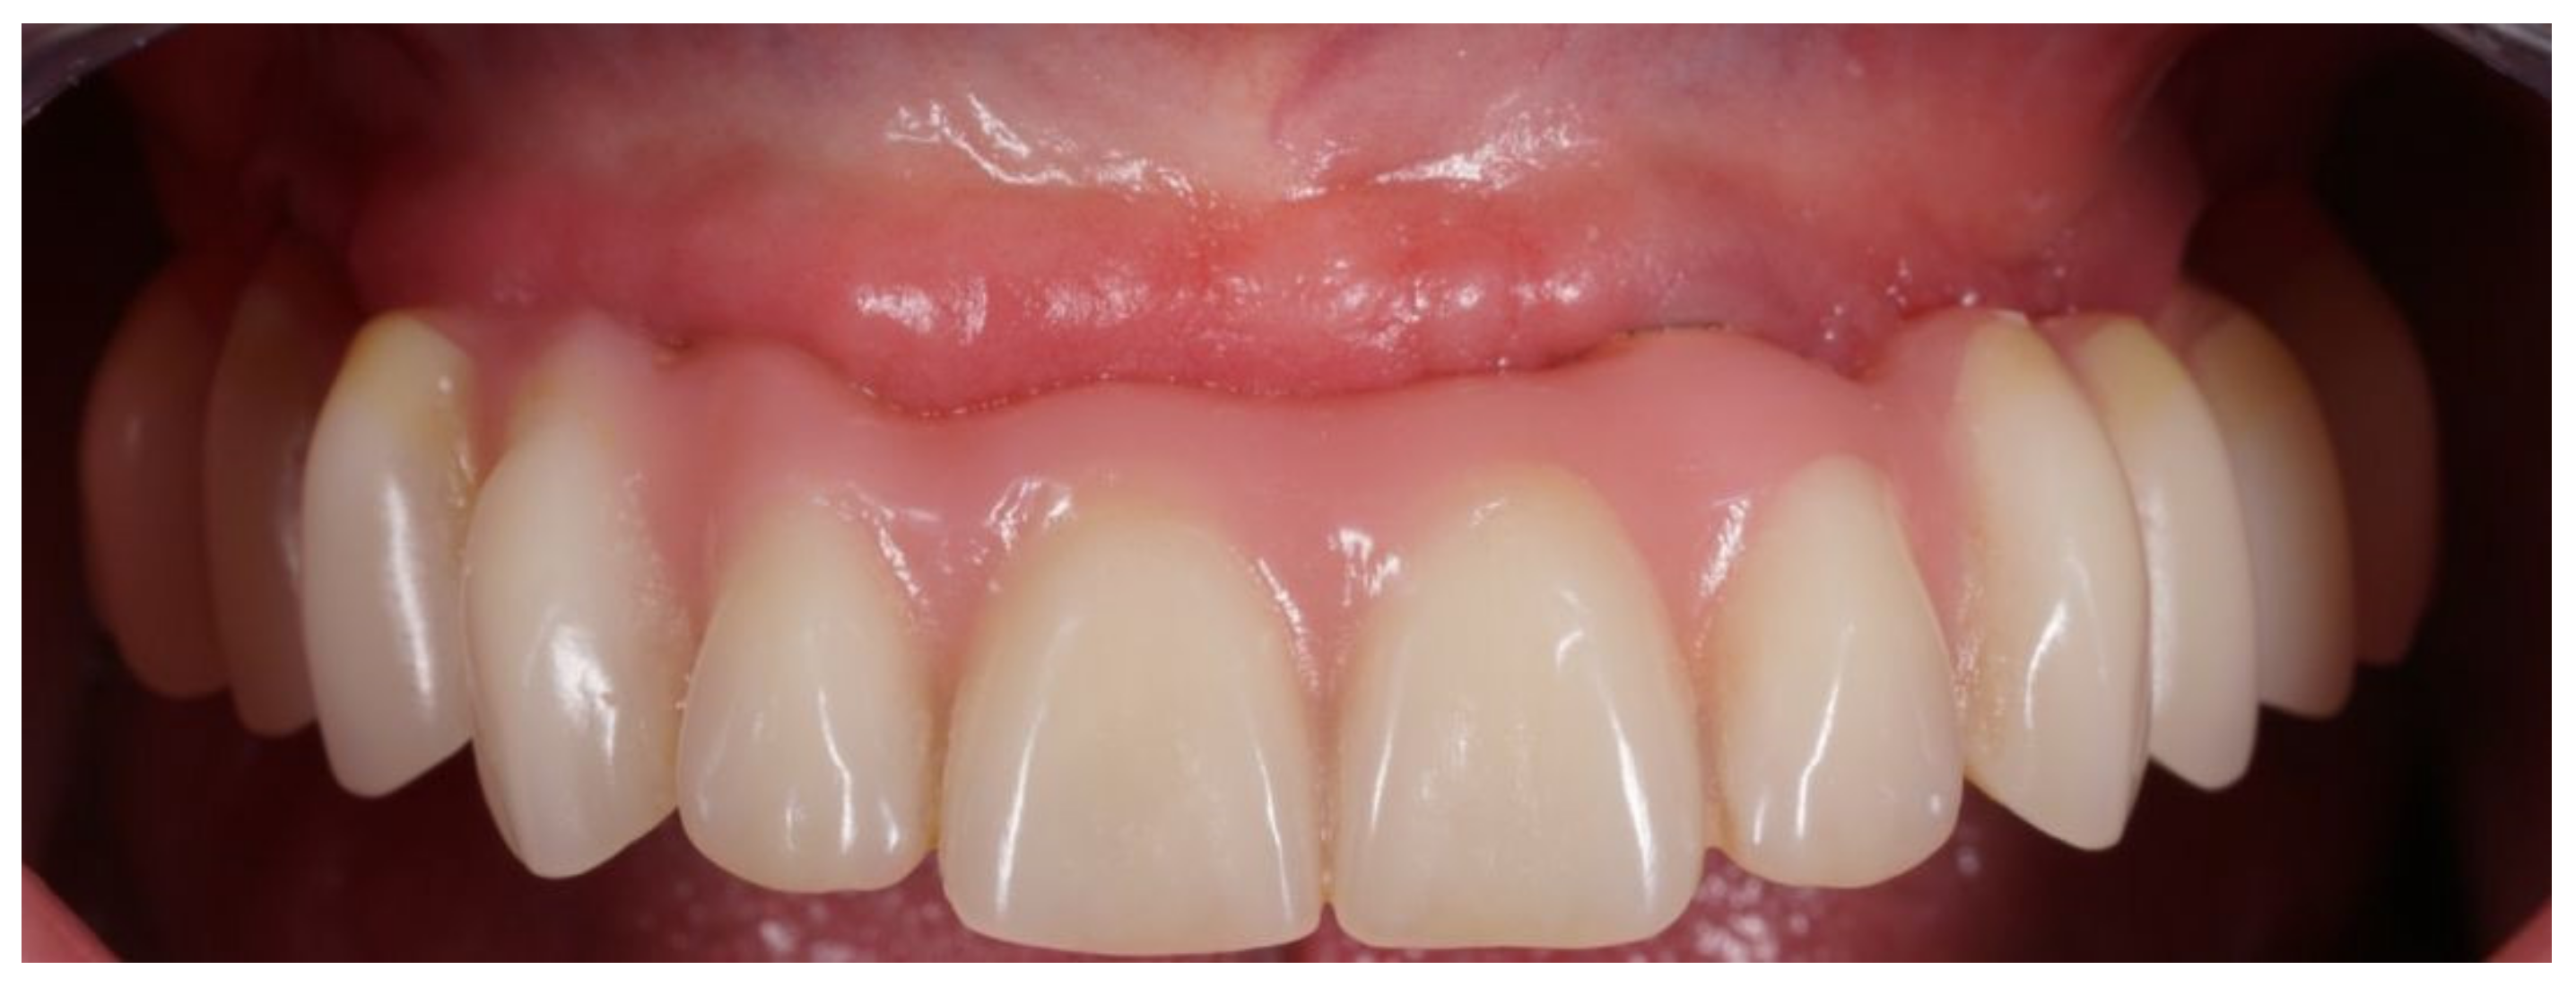

Figure 6.

Definitive prosthesis with cantilevers after 7 years of use.

Figure 7.

Occlusal view of definitive prosthesis after 7 years of use.